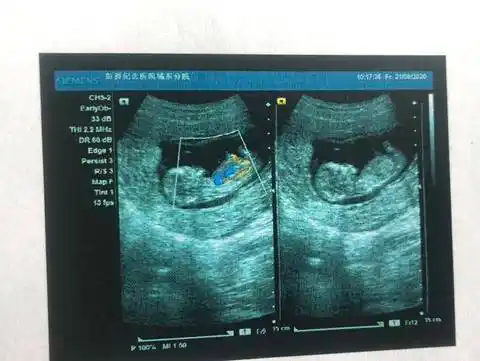

可以看出男孩女孩吗?12周